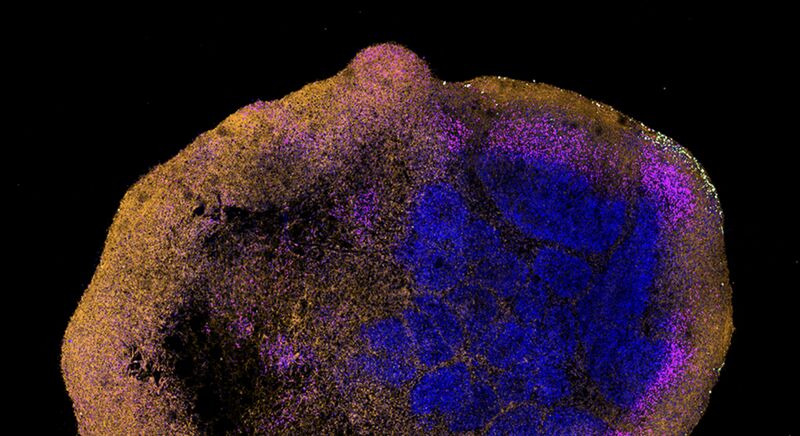

Researchers, including Isabel Schultz-Pernice and Prof. Dr. Marco P. Alves from the University of Bern, the Institute of Virology and Immunology IVI, the University of Lausanne, and the Spiez Federal Laboratory, have shown that the monkeypox virus (MPXV) efficiently spreads between cells in human brain organoids, causing significant neuron death. This discovery reveals the virus's potential to harm the human central nervous system and highlights the urgent need for further study into its effects on the brain. The finding that MPXV can destroy neurons without damaging surrounding tissues deepens our understanding of its threat to our health. Using 3D tissue models from human stem cells, the team replicated brain features to observe MPXV's behavior. They infected these organoids with a virus sample from a 2022 outbreak patient and used advanced imaging to watch the virus move through neurons. This research not only proves brain organoids as a valuable, ethical alternative to animal testing but also suggests potential treatments. For example, the antiviral drug Tecovirimat significantly reduced the infection in this study, offering hope for combating MPXV's neurological effects.